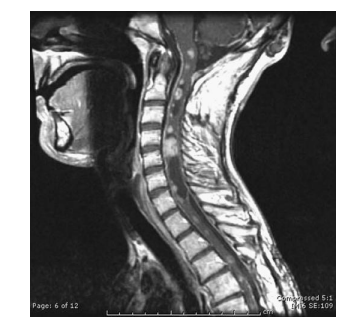

A 39-year-old presents with a 6-month history of tingling in her fingers and in the last few months, her legs. There is no bowel or bladder disturbance. On examination, there is cape-like pattern of pain and temperature loss in her upper limbs. Upper limbs are weak distally 4/5, and reflexes are globally brisk with extensor plantar responses bilaterally. MRI is shown. Which one of the following is most likely?

a—Astrocytoma

A 39-year-old presents with a 6-month history of tingling in her fingers and in the last few months, her legs. There is no bowel or bladder disturbance. On examination, there is cape-like pattern of pain and temperature loss in her upper limbs. Upper limbs are weak distally

4/5, and reflexes are globally briskwithextensor plantar responses bilaterally. MRI is shown. Which one of the following is most likely?

a. Astrocytoma

A

Astrocytomas are the second most common intramedullary spinal cord tumors in adults (30%),

compared to children in which they are the commonest. Almost 60% of these tumors occur in the cervical and cervicothoracic region, and 20%

have an associated syrinx. Back pain and motor

deficits are the most common presenting symptom in astrocytomas. The most significant prognostic factors in patients with primary spinal cord

astrocytoma are tumor histology, tumor grade,

age, and performance status. Because of the rare

nature of this disease, almost all data are based

on retrospective reviews fraught with selection

bias. Therefore, neither the extent of resection

nor treatment with adjuvant irradiation appears

to be prognostic, although this is controversial.

The classic MRI appearance of intramedullary

astrocytoma is cord enlargement with a central

lesion with poorly defined margins, cysts, peritumoral edema and patchy enhancement (no

enhancement in 30%). It is typically isointense

to hypointense on T1-weighted images and

hyperintense on T2-weighted images. The treatment of choice for intramedullary astrocytomas is complete excision of the tumor, when it can be safely accomplished without neurologic compromise. Otherwise, an incomplete excision is typically performed for grade I lesions, and biopsy alone is the surgical strategy for the

non-exophytic component of an infiltrative glioma. GTR is typically extremely difficult to

achieve because of the infiltrative nature of all

but the pilocytic lesions, with most authors

reporting a 0-50% likelihood of GTR for spinal

cord astrocytoma. In patients with favorable

prognostic factors (low-grade histologic findings,

good performance status, and young age), observation with serial imaging studies, reserving irradiation for local recurrence, is an appropriate

management option, particularly for young children. Radiation should be considered for highgrade tumors, inoperable tumors, tumors remaining after surgery, and recurring tumors. In the remainder of patients, adjuvant irradiation is

usually recommended because progression of

tumor in the spinal cord may lead to significant

neurologic impairment. The overall outcomes

are similar for patients with low-grade gliomas

of the spinal cord treated either by GTR or

STR or biopsy followed by external beam irradiation (EBRT), with most series reporting OS at

5 years of 55-100%. With high-grade tumors in

adults and children, the median survival time is

quite poor (4-10 months) despite surgery and

EBRT. Extrapolating from the results of Stupp et al. for intracranial glioblastoma, temozolomide

has emerged as a treatment strategy in high-grade

intramedullary tumors